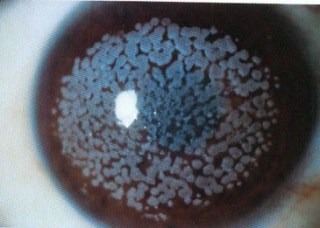

El transplante de córnea es un procedimiento quirúrgico en el que se busca reemplazar la córnea enferma del paciente por una córnea sana de un donante.

El tipo más común de trasplante es el de espesor completo o «penetrante» en el cual se reemplaza toda la córnea.

Además existen otros tipos en los cuales se puede reemplazar solo el sector enfermo, como es el caso de la queratoplastia lamelar anterior (DALK) o posterior (DSAEK).

Es una cirugía que requiere controles postoperatorios frecuentes y tratamiento prolongado con gotas para prevenir el riesgo de rechazo corneal.